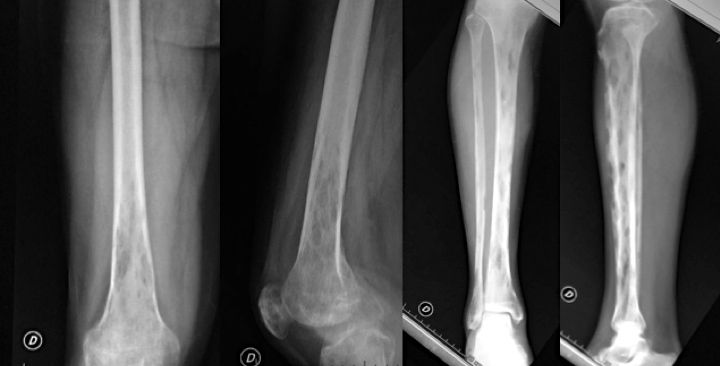

Paciente de 38 años de sexo masculino, sin antecedentes médicos a destacar. Predsentaba dolor, de 6 meses de evolución, en el miembro inferior derecho, con aumento de tamaño e impotencia funcional progresiva. Se realizaron radiografías de todo el miembro presentando lesiones osteolíticas multifocales que comprometían el tercio distal de fémur, la rótula y la tibia en toda su extensión. Dichas lesiones presentaban limites mal definidos, con una amplia zona de transición que erosionaba la cortical anterior de la tibia. En la paraclínica no se encontraron alteraciones.

Se realizó un TC de miembro inferior derecho que mostró lesiones líticas redondeadas con compromiso cortical y expansión a partes blandas. El body TC no mostró alteraciones y la RNM se presentó como lesiones de señal intermedia en T1 e hiperintensas en T2. Se realizó un PET Scan que presentó un patrón atigrado desde tercio distal de fémur al tarso. Se efectuó una biopsia guiada por TC por imagenólogo, sin obtener una muestra adecuada. El paciente presentó dolor intenso con agravación de los síntomas siendo necesaria la administración de opioides para analgesia. Se decidió realizar biopsia por punción con aguja gruesa de fémur distal y tibia, bajo intensificador de imágenes que se enviaron al servicio de anatomía patológica. El informe señaló el diagnóstico de tumor vascular óseo primario del tipo de HEE. Se realizó CT óseo luego de la biopsia sin onservar un aumento de las lesiones.

El equipo multidisciplinario decidió conjuntamente realizar una amputación transfemoral media de miembro inferior derecho y solicitar consulta con equipo de radioterapia en vistas a irradiar el fémur remanente. Se realizó la cirugía sin complicación con un protocolo previo de pregabalina para disminuir los síntomas de miembro fantasma. La evolución posoperatoria fue buena con cierre del muñón sin complicaciones. La pieza de amputación fue de 132 cm de longitud, incluyendo la porción media y distal del muslo con la pierna y el pie. Macroscópicamente el fémur presentó una lesión diafisaria de 10 x 15 mm que incluía también parte de la metáfisis. En el extremo proximal y en la diáfisis tibial se observaron lesiones de 15 a 35mm. En la microscopia se observaron lesiones óseas con proliferación vascular, con células de aspecto epitelioide dispuestas en cordones y aisladas, algunas de aspecto fusiforme. La proliferación invadía el plano muscular de la pierna. Actualmente lleva 8 meses de evolución tras la cirugía con una cicatrización excelente del muñón de amputación y sin dolor ni síndrome de miembro fantasma.